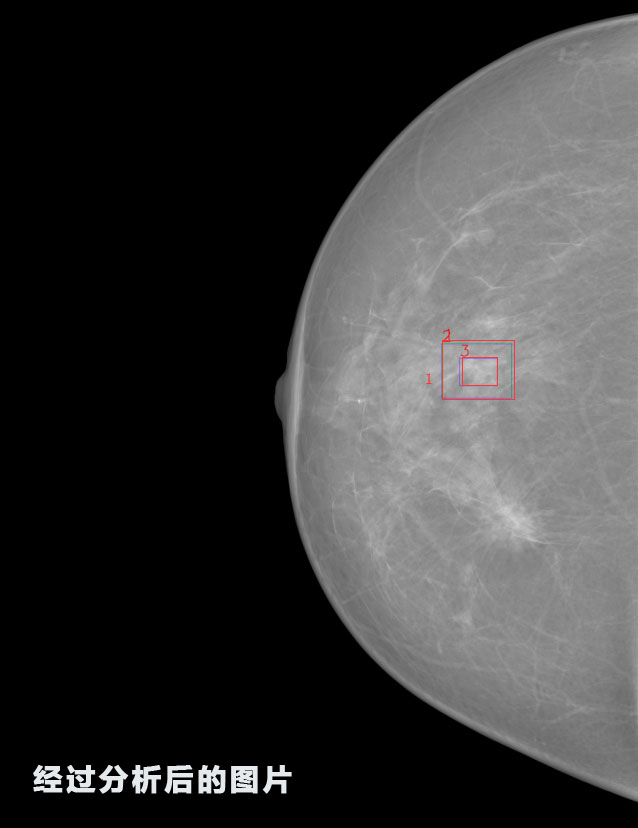

識別報告:

1.發(fā)現(xiàn)良性鈣化,可能性為19.88%---位置框指數(shù):[1796.0867 1359.8237 2058.1372 1582.5334]

2.發(fā)現(xiàn)惡意鈣化的可能性為15.18%---位置框指數(shù):[1789.4733 1365.9951 2063.7698 1576.0613]

3.發(fā)現(xiàn)惡意鈣化的可能性為12.45%---位于框指數(shù):[1859.3987 1422.3184 2006.5494 1528.2698]